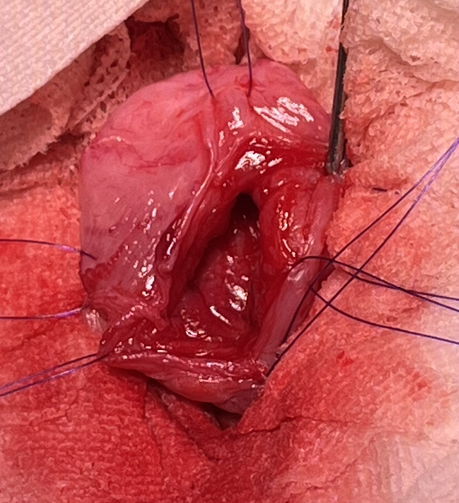

以下、手術時の写真となります。苦手な方はご注意ください。

膀胱を切開し結石を取り除きます。

摘出された結石はシュウ酸カルシウムでした。